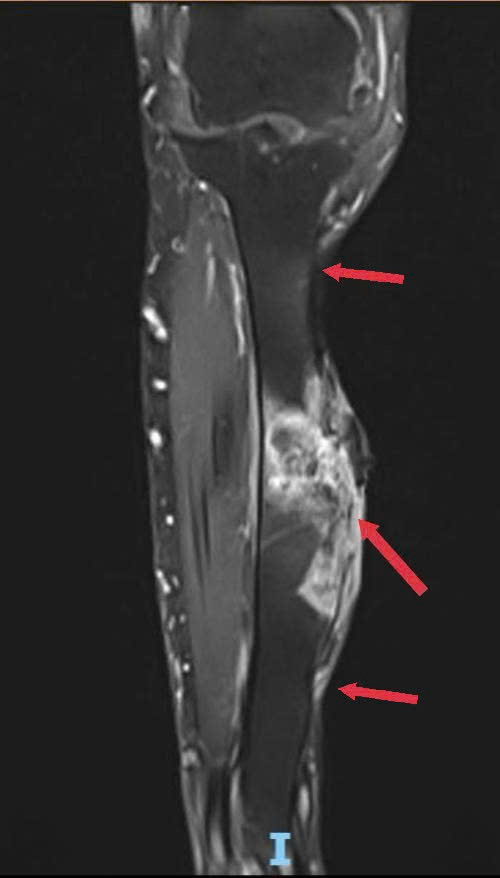

Hình 2: Diện xương chày xâm lấn trên MRI (hình ảnh tang giảm tín hiệu), 2 mũi tên ở trên và dưới là ranh giới phần xương được cắt bỏ trong phẫu thuật